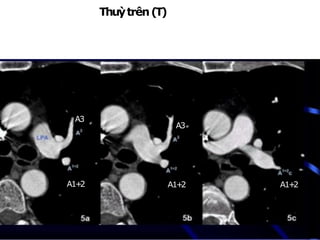

Thuỳtrên(T)

NhánhA1+2:từ mặttrênĐMphổi (T)đi lêntrên

NhánhA3:đi ratrước

A3

A1+

2 A1+

2